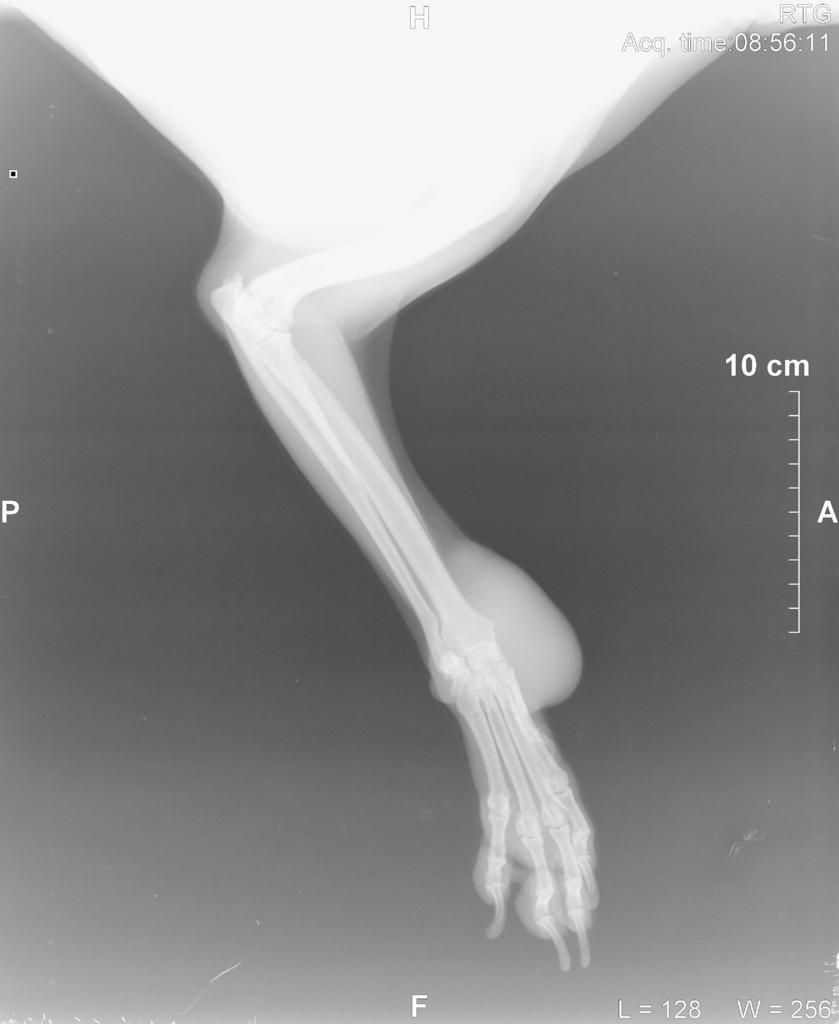

Dodalem w pierwszym poscie rtg z dzisiaj i rtg z 05.02.2014 (5miesiecy wczesniej to zdjecie w srodku)

[COLOR=#000000][FONT=Verdana]Witam, moja 10 letnia sunia ma taka wielka narosl na lapie.. ani to ja nie boli nie kuleje ani nic.. jest to miekkie, na poczatku jak bylo male byl robiony rentgen ale nie bylo zadnych zmian patologicznych.. macie moze pomysl co to moze byc? w zalaczniku dalem zdjecie lapy. kostniakomiesak a moze tluszczak? nie wiem co tym sadzic.. w zalaczniku dalem zdjecie lapy psa.. prosze o rady i pomoc ;)[/FONT][/COLOR][attachment=3445:11639.attach]

tak wiem. Tylko jest problem bo lapa jej puchnie.. wyglada jak u niedzwiedzia.. ;/ jak wet sciaga krew zeby sie skrzep nie zrobil to po godzinie lapa wyglada znowu tak samo ;/